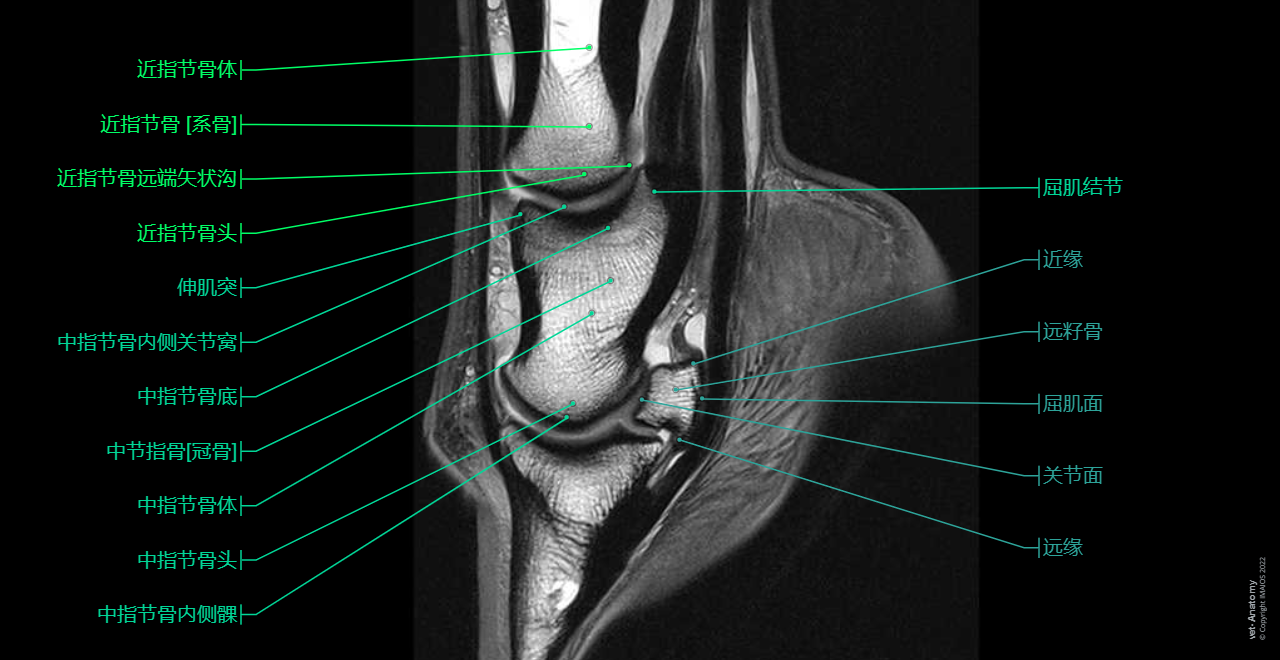

Anatomy of the equine digit (MRI): MRI - PD - Sagittal (Proximal phalanx [Long pastern bone], Middle phalanx [Short pastern bone], Distal phalanx [Ungual bone; Coffin bone; Pedal bone])

这单元展示马足趾(马蹄、足和骹)核磁共振MRI解剖图。

这单元的马足趾核磁共振解剖图是由Gwendolyn J. Levine(DVM, DACVP)提供。德克萨斯A&M大学的兽医与生物医学学院使用Siemens Verio 3T核磁共振机器扫描美洲奎特马正常左前腿。